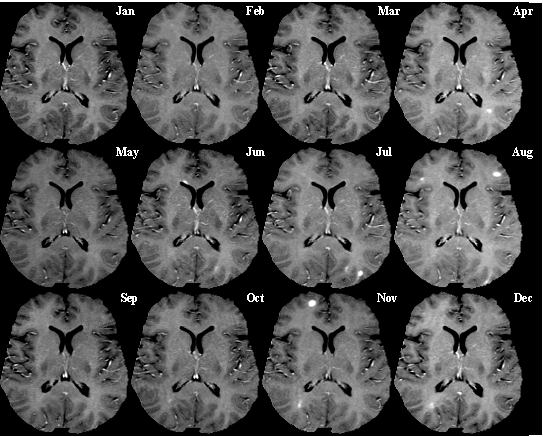

Multiple Sclerosis: T1-weighted MRI (post-contrast) of same brain slice at monthly intervals. Bright spots within the brain tissue indicate active lesions. |

U.S. Brookhaven National Laboratory: Quantitation of Blood-Brain Barrier Permeability in MS Lesion Development |